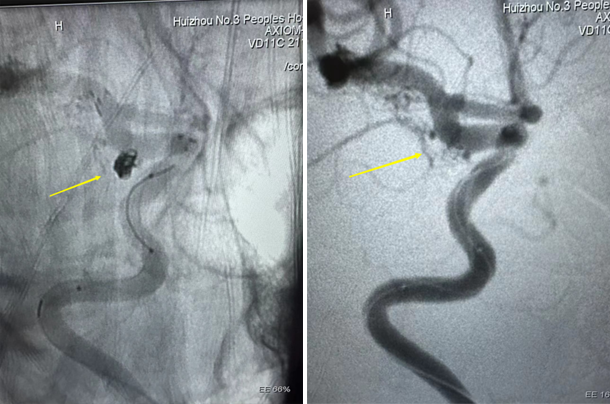

通過急診造影,醫(yī)生明確了左側后交通動脈瘤為“責任”動脈瘤,景英朝主任醫(yī)師與溫一奇副主任醫(yī)師結合DSA結果及病人特殊情況,迅速制定手術策略——急診行血管內介入栓塞治療!

即使患者年齡大、基礎病多、血管條件差,介入團隊仍經過多次努力嘗試、歷經數(shù)小時的奮戰(zhàn),使動脈瘤終于栓塞成功,避免了再次出血的風險。術后,陳奶奶返回神經外科重癥監(jiān)護病房,進行下一步治療。目前,陳奶奶生命體征穩(wěn)定,正在后續(xù)治療中。

栓塞術后